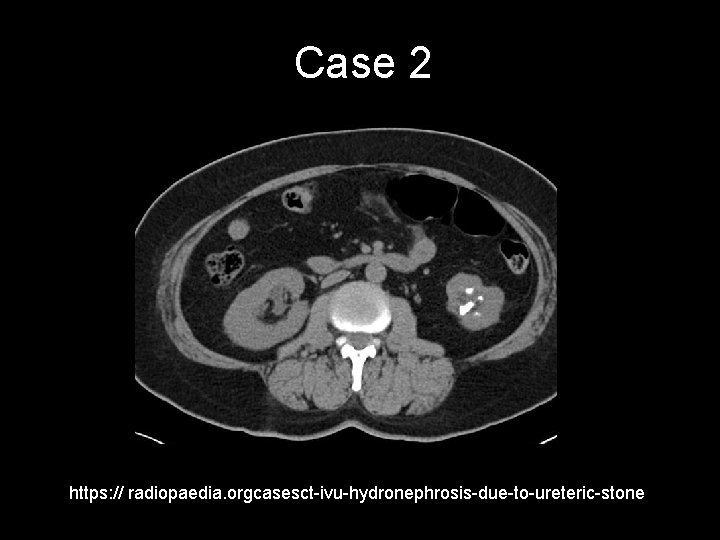

Acute Onset Flank Pain Case 2 -Acute flank pain - No fever - Recurrent symptoms of stone disease

Case 2 • First study? – X – ray intravenous urography – MRI abdomen and pelvis without and with contrast – MRI abdomen and pelvis without contrast – US kidneys and bladder retroperitoneal with Doppler – CT abdomen and pelvis without contrast – CT abdomen and pelvis without and with contrast

Acute Onset Flank Pain Case 2 Patient with right sided renal colic and a history of renal stones https: // radiopaedia. orgcasesbilateral-renal-stones

Case 2 https: // radiopaedia. orgcasesct-ivu-hydronephrosis-due-to-ureteric-stone